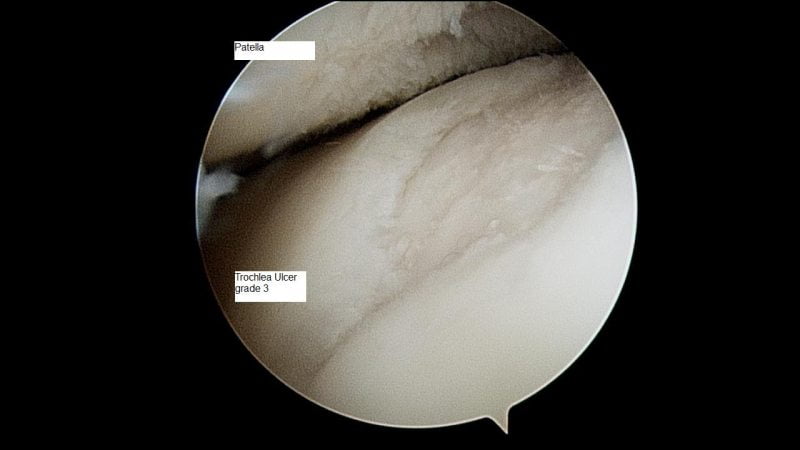

Артроскопия показана для обследования внутренних поверхностей сустава. Через проколы мягких тканей в его полость вводится миниатюрное устройство с видеокамерой. Изображение с нее поступает на экран прибора. При необходимости сразу производится удаление накопившейся жидкости с дальнейшей обработкой антисептическими растворами.